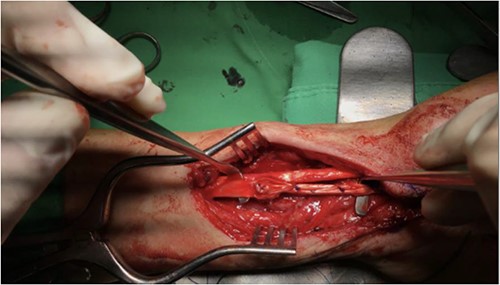

Pre-operative assessment was performed, and remove volar plate, tenolysis, release of flexor retinaculum and tendon graft reconstruction of FPL were performed on 1 November 2022, due to total severance with adhesion and fibrosis (Fig. 4). Post-operative pain control was given, and wound dressing was changed regularly. No fever or wound dehiscence was noted during her hospital stay. A rehabilitation specialist was consulted for a spica splint, and the Penrose drain was removed on 3 November 2022. She was discharged on 3 November 2022, in stable condition.

Post-operative photo showing removal of volar plate, tenolysis, release of flexor retinaculum and tendon graft reconstruction of FPL that were performed on 1 November 2022.